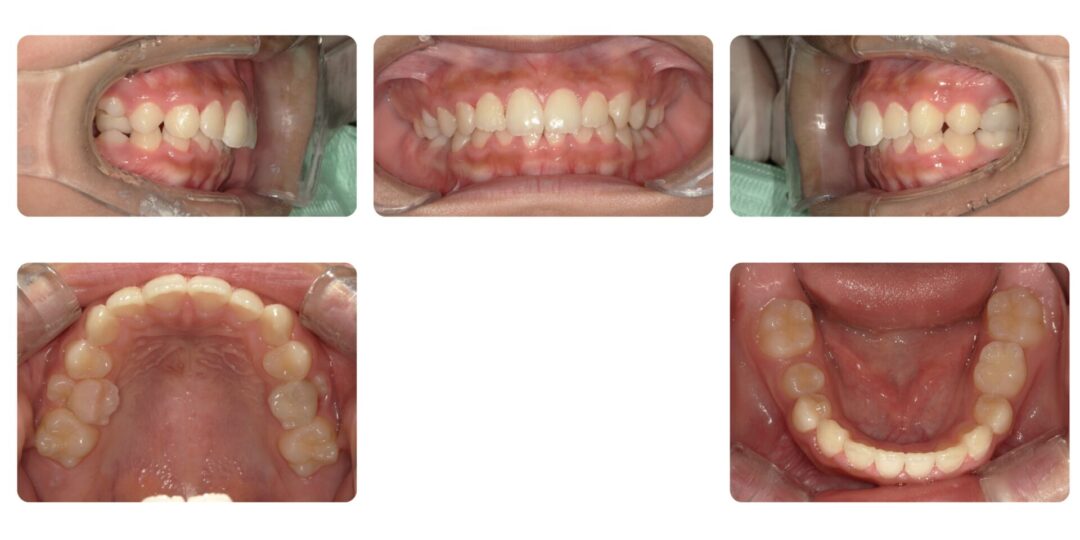

矯正治療後

ご相談内容

下の前歯がガタガタしている

初診時11歳

治療内容

第一期治療 拡大床による歯列矯正→部分的にブラケット装置矯正

治療期間

2年7ヶ月

治療費用

自由診療 基本料金¥330,000 処置料¥3,300(ブラケット期間は¥5,500)